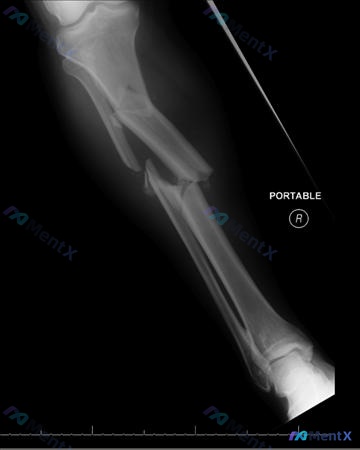

整理到一个左前臂桡骨骨折术后复查的影像相关讨论点,大家看看这种情况会怎么判断: 基本背景 - 左前臂桡骨骨干骨折,已行切开复位内固定术 - 本次复查为左前臂侧位X光片 影像观察到的客观表现 - 桡骨背侧可见金属接骨板及数枚螺钉,位置固定,未见明显松动、断裂或移位 - 骨折断端区域有骨痂生长,骨折线模...